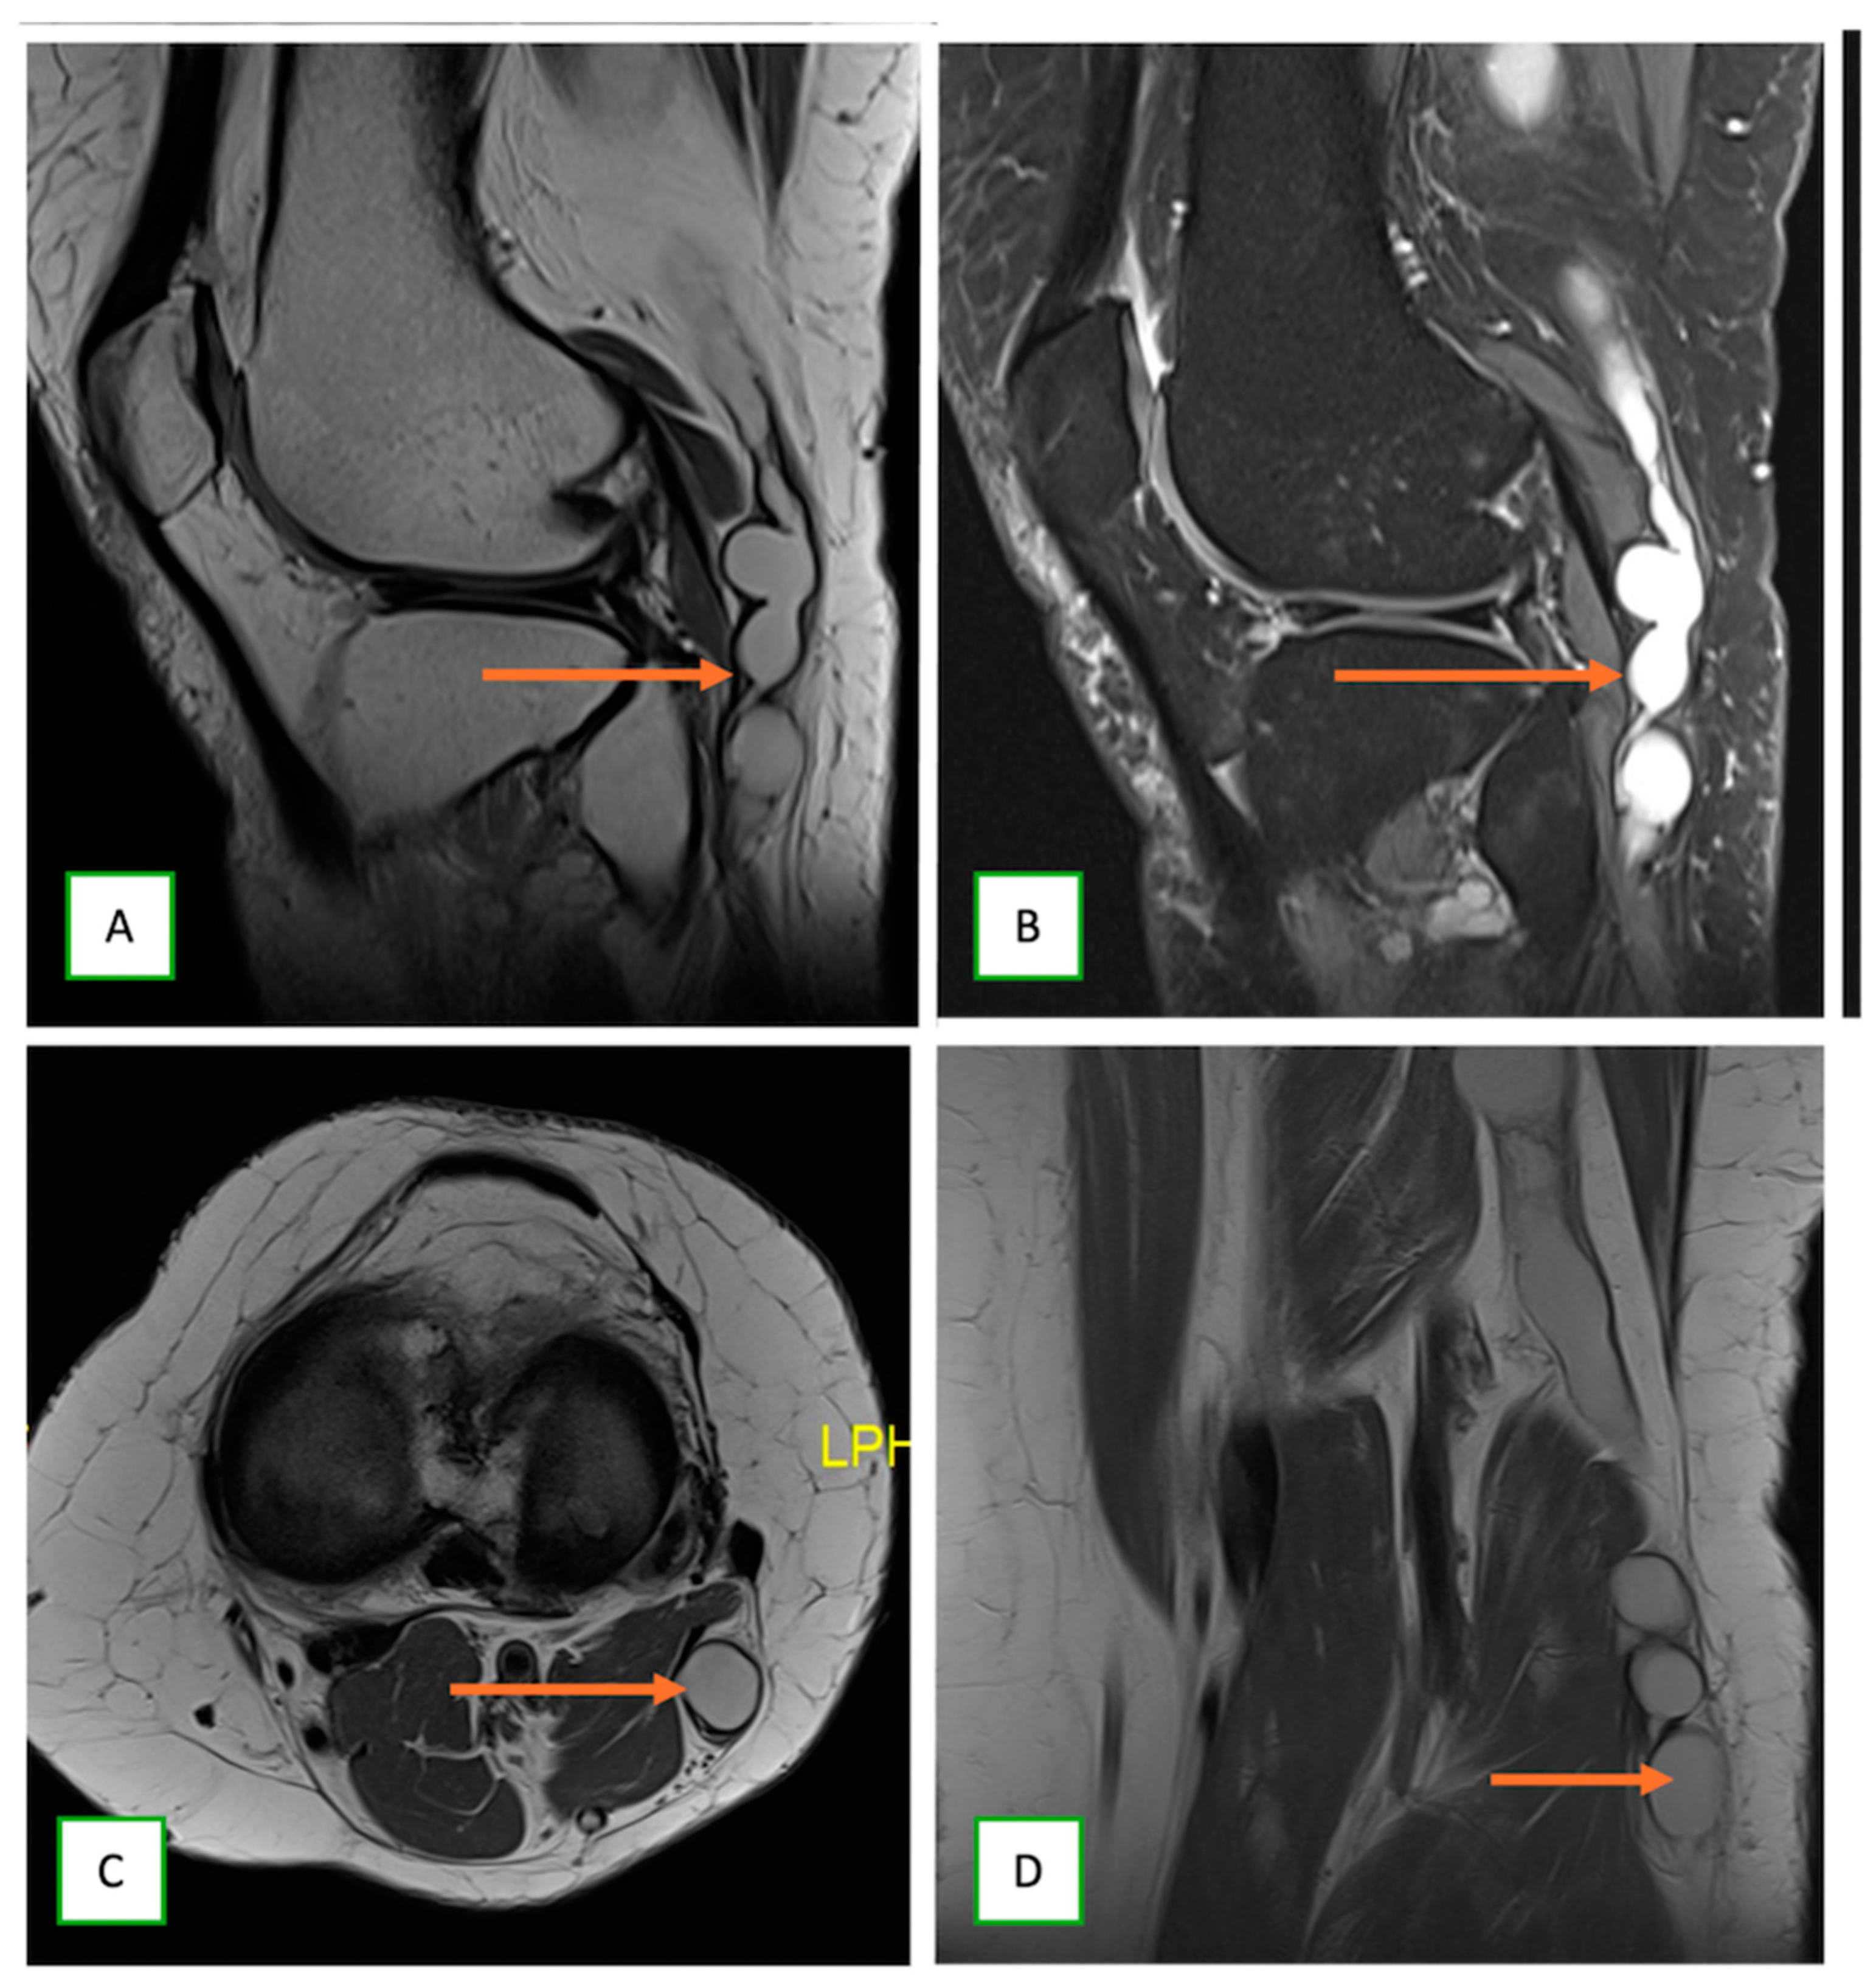

- Primary Sarcomas: Soft-tissue sarcomas are uncommon, accounting for just over 1% of adult malignancies. Synovial sarcoma, clear cell sarcoma, and epithelioid sarcomas are known to involve peripheral nerves. CT/MR reveals a large soft tissue mass with areas of necrosis or calcification and heterogeneous contrast enhancement. F-18 FDG uptake is useful for both tumor staging and treatment assessment (Figure 26, Figure 27 and Figure 28).